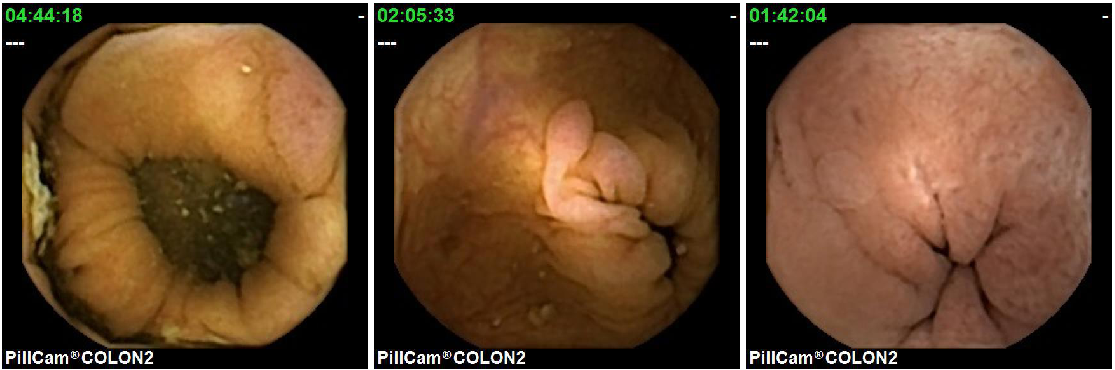

The second important point to consider when creating the database and its evaluation methodology, is that although all polyps have common visual characteristics, the appearance of different polyps from the same patient must be considered. The first row of Figure 5 shows three different polyps from the same patient, while the second row shows three polyps from different patients. As it can be observed, those polyps from the same patient are generally similar in shape and texture while the polyps from other patients are more diverse. It is for this reason, that training and test set must not use images from the same procedures.